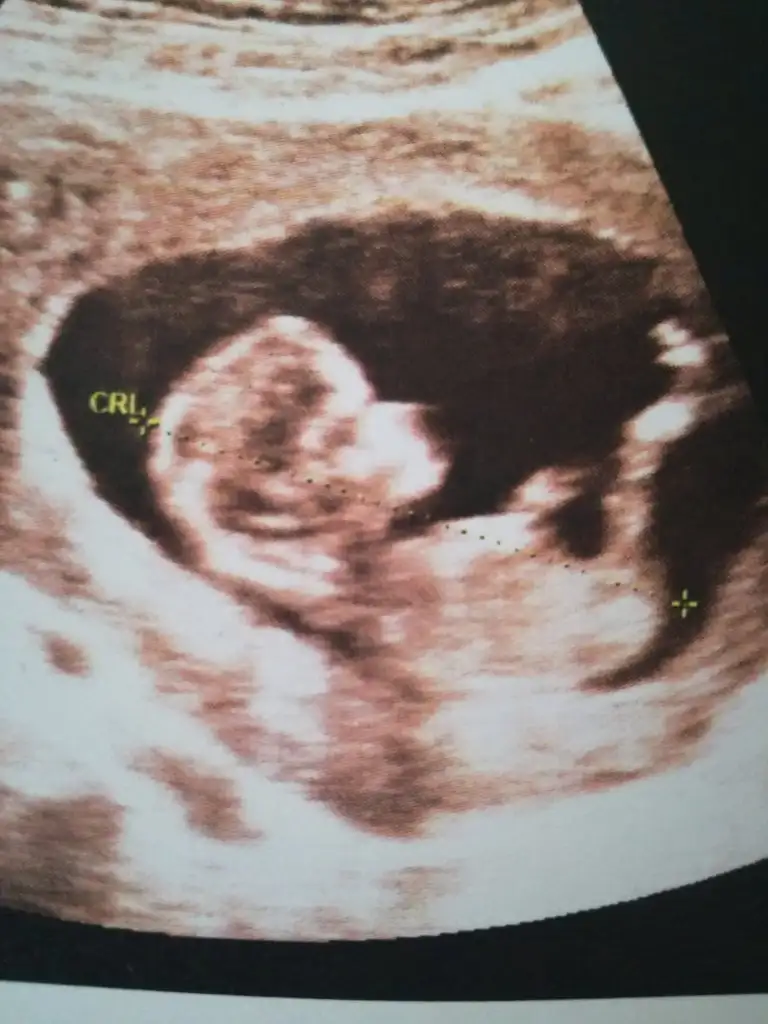

yaa lütfen bana da bi tahminde bulunsanız.Bi oğlum var bide kızım olsun çok istiyorum ama sağlıkla gelsin inşallah tabi en önemlisi o.Çokta merak ediyorum 11+4 şuan

Eklentiler

• IMG_20190823_182529.webp

29,9 KB · Görüntüleme: 62